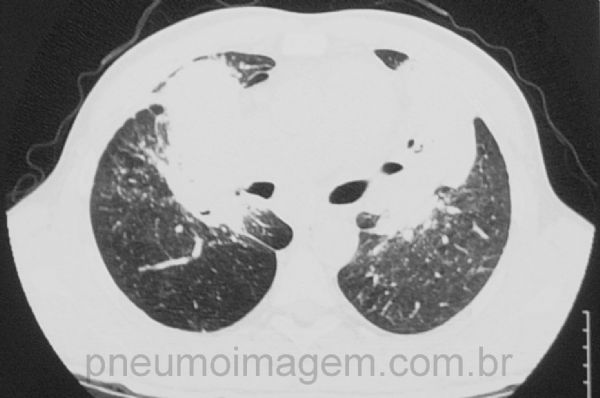

Neste corte tomográfico se observam as massas conglomeradas de fibrose e alguns nódulos centrolobulares.

In this CT slice are observed conglomerate masses of fibrosis and few centrilobular nodules.